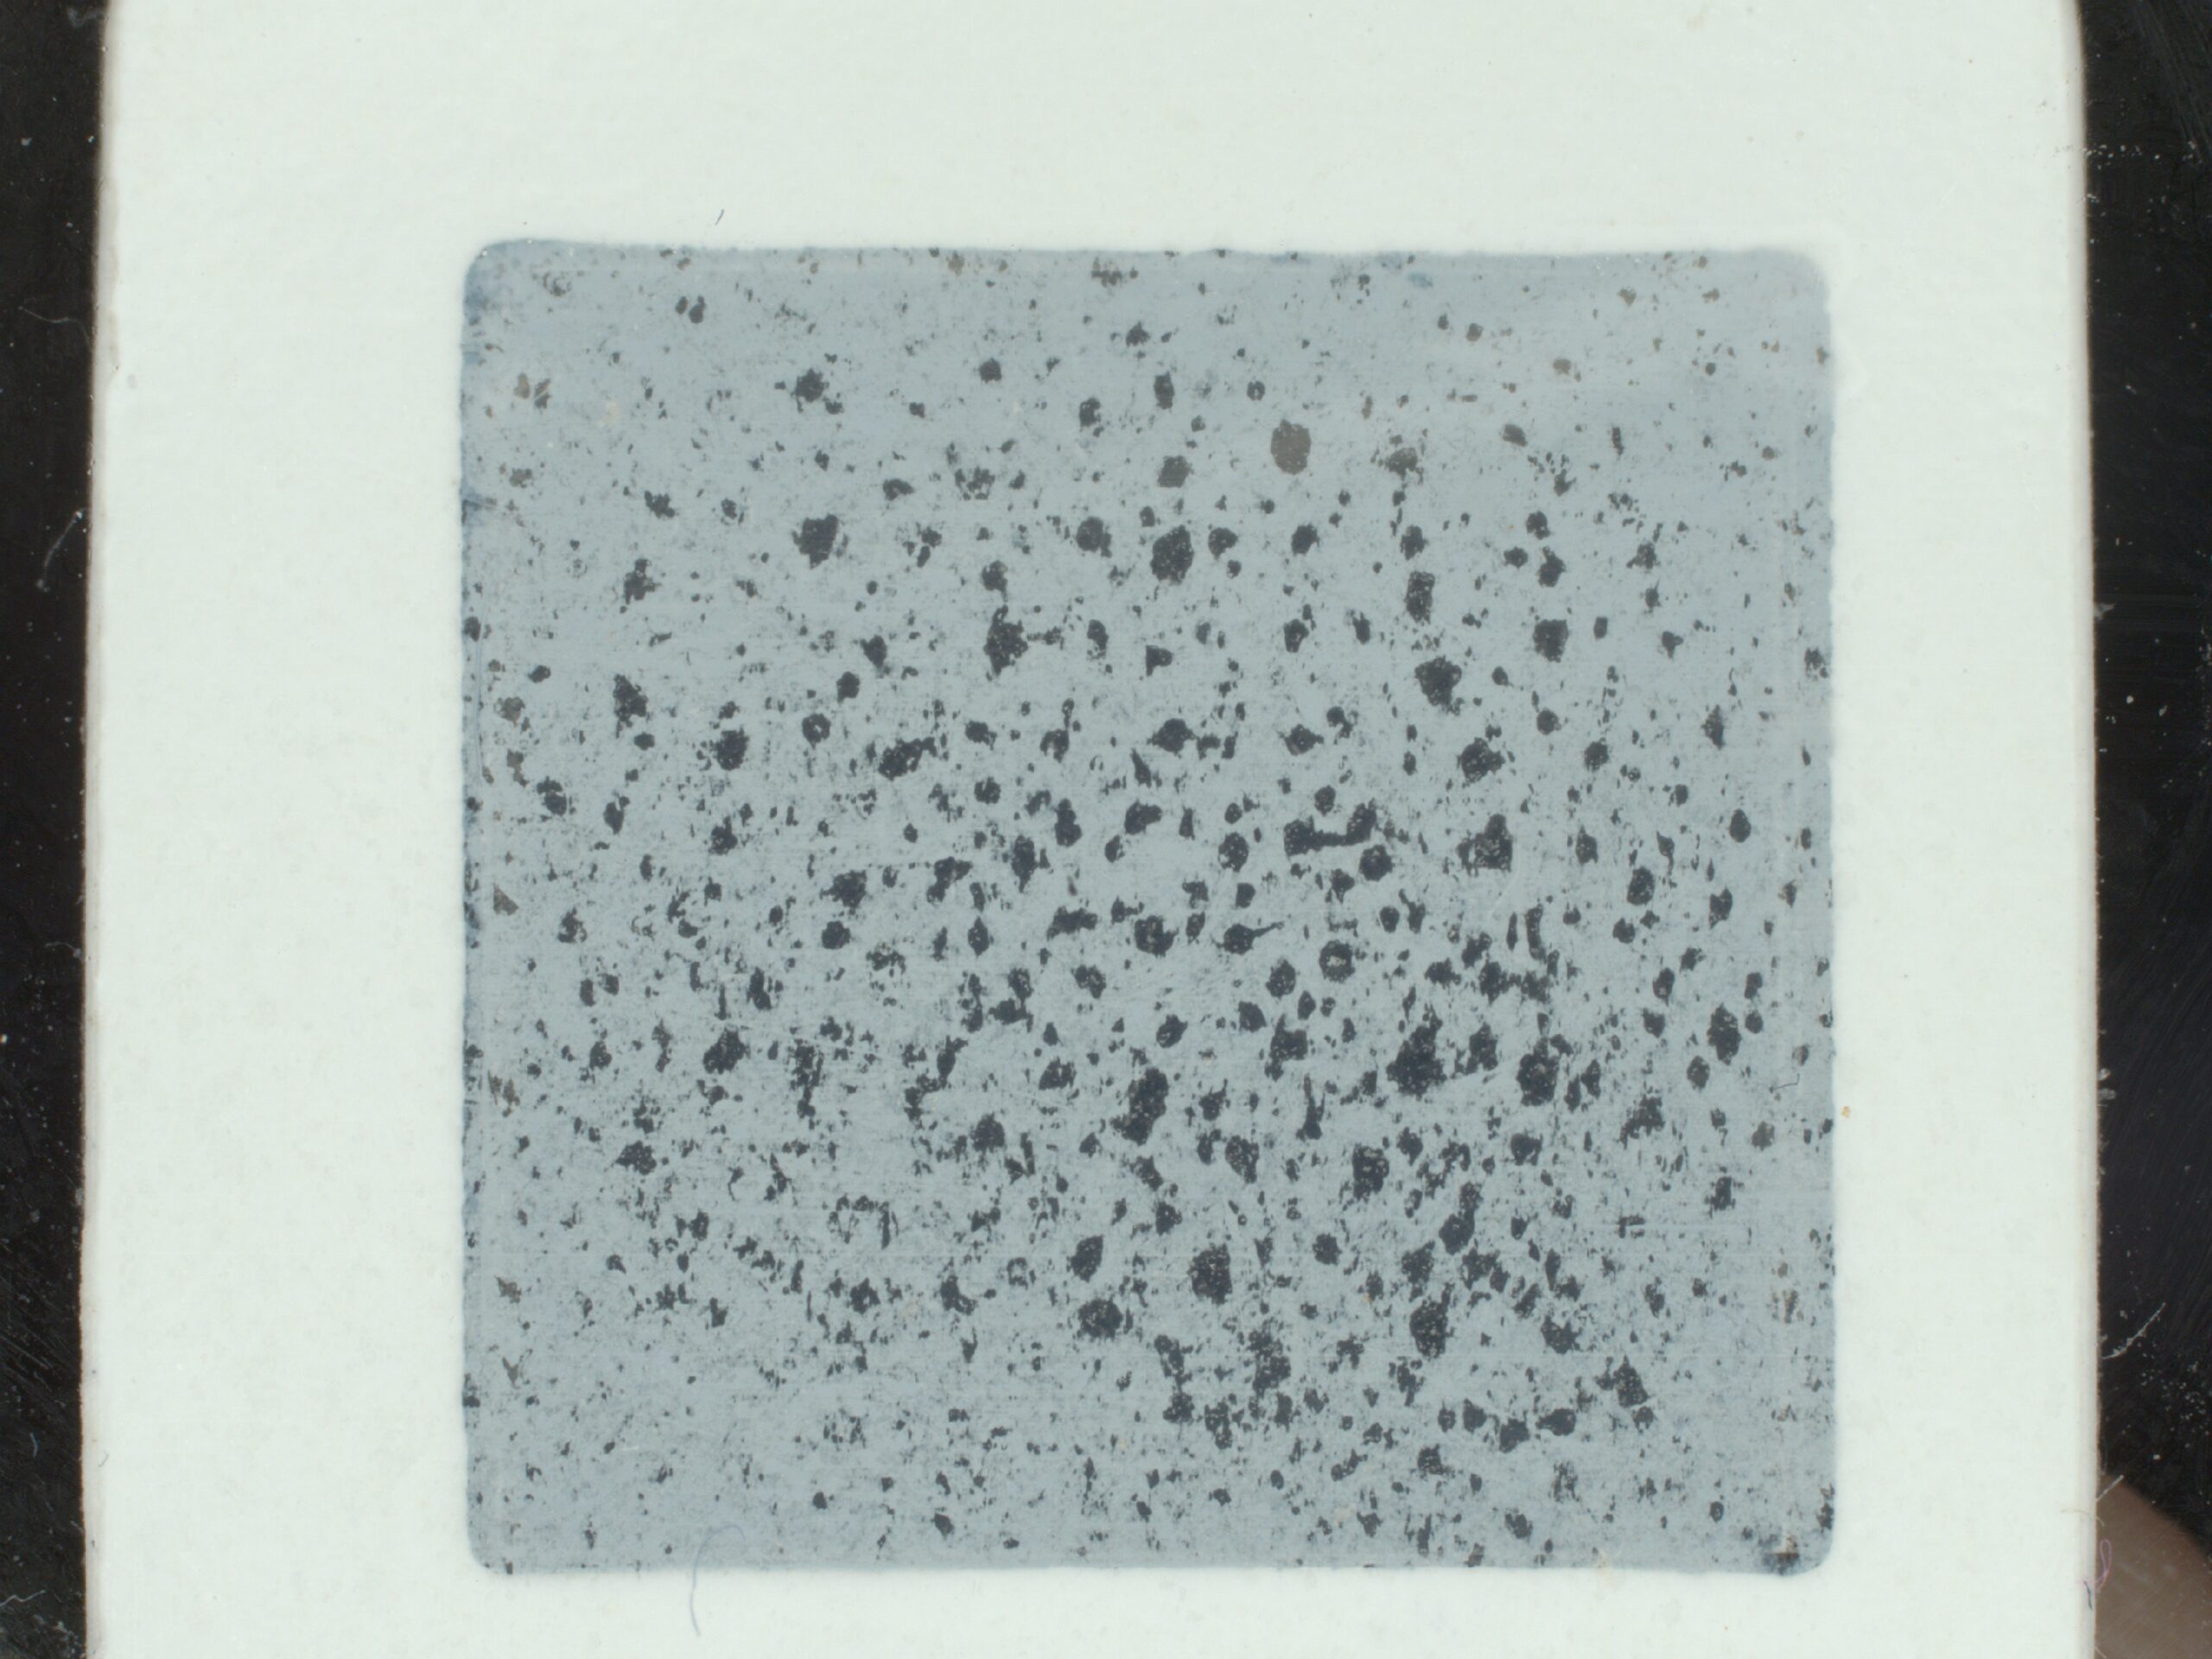

The color of the sample area is gray and uniform, so that dark sebum patches can be clearly distinguished. Samples taken from these patches are analyzed with the Pixience sample reader and C-Cube camera in a standardized, systematic way. By analyzing the intensity levels in the sample area, we can determine a threshold between the “background” (the gray area of the sample) and the “form” light intensity (the black area, i.e. the sebum).

This makes it easy to distinguish between them and measure the relative surface area of sebum in relation to the total surface area of the spot (expressed as a percentage of the total surface area).